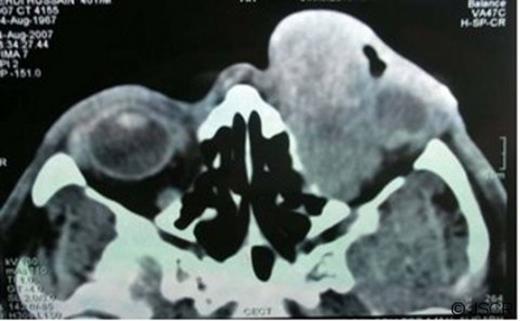

A forty year old male presented to us with loss of vision, pain, swelling and bleeding of the left upper eye lid for the past three months. There was a 1 year history of a small swelling on the left upper eyelid. On ocular examination no light perception was present. A left upper eye lid swelling of 4.0 cm×2.5cm with an ulcerated wound on the nasal aspect of lid margin was seen (Fig 1a). On general examination no lymphadenopathy or organomegaly was detected. A differential diagnosis of sebaceous gland carcinoma, squamous cell carcinoma, or preseptal cellulitis was made. Contrast enhanced computed tomography (CECT) showed an ill defined heterogeneous soft tissue density mass (6.0cm×3.0cm×3.6cm) in the left orbit involving both extraconal and intraconal space. In the intraconal space, the mass was extending deep in the orbit encasing the whole of the optic nerve. There was also a displacement and deformation of the globe laterally (Fig 1b).

left upper eyelid swelling with an ulcerated wound on its nasal aspect.